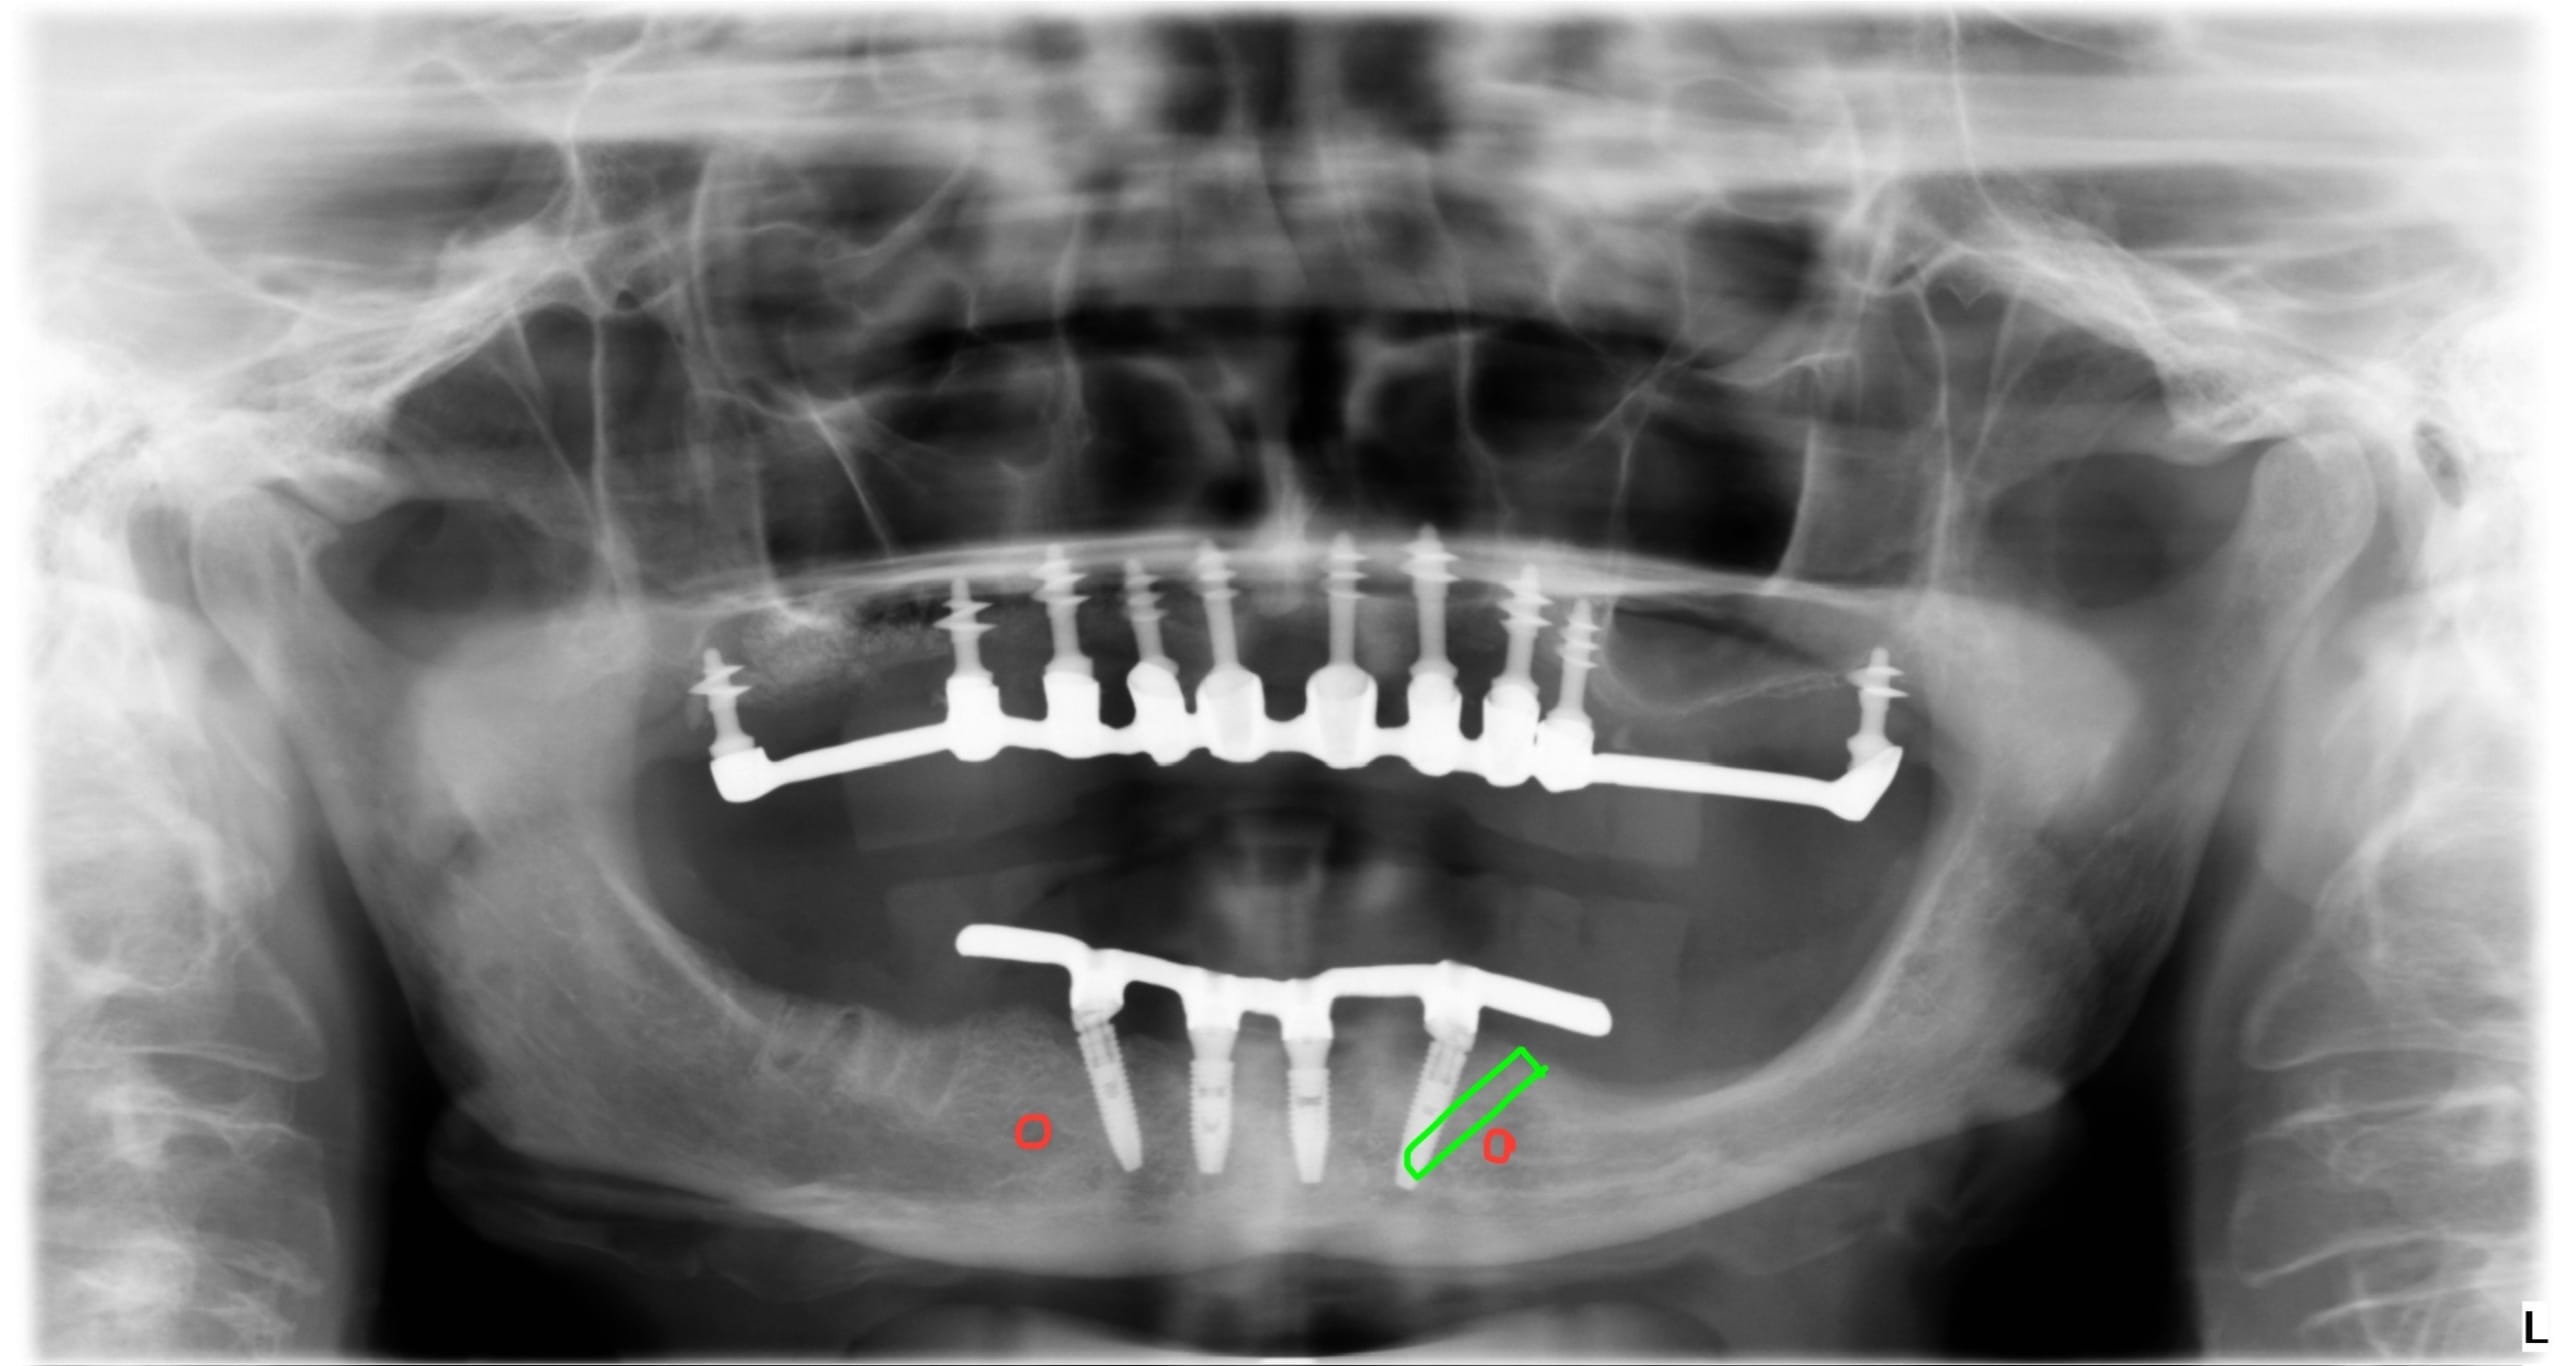

Kaptam néhány fotót, köztük egyet a legutóbbi sérülésről és egy panoráma felvételt.

1. pontosabb mérést kell végezni a fopótlás rágófelszínén…de biztos, hogy túldimenzionálták hátrafelé a rágófelszínt. A túlzott hátsó túlnyúlás miatt túl nagy húzóerő lép fel az első implantátumokon, mely

2. kitépi a túl rövid és beragasztott ideiglenes(!) titán hüvelyt* a fogpótlásból. Bár fémváz van a műíny alatt, de az implantátumokhoz csavarozott titán hüvelyek nem a fémvázzal egyben vannak kimarva / öntve, hanem – egy jóval olcsóbb megoldásként, a fogpótlás csavarozhatóságát biztosítandó – ideiglenes titán hüvelyeket ragasztottak a fogpótlásba. A túl rövid titán hüvely nem tud elég hosszan rögzülni a fogpótlásban: ez egy ekkora hátsó túlnyúlással nem tud már megbírkózni.

Ami szinte még biztos hiba / probléma (szokott lenni): szinte mindenütt átlagos fogsor alaplemez (rózsaszín műíny) alapanyagot és műfogakat alkalmaznak, melyek szeretnék kitörni. Mert olyan erők ébrednek egy ilyen fogpótlásban, melyeket “elviselnI” nem alkalmasak az átlagos protézis alkotóelemek. Erre gyártanak speciális, sokszorosan erősebb alaplemez alapanyagokat és műfogakat – de ezek sokszorta drágábbak és nehezen beszerezhetők hazánkban.

Fenti megoldást (öntött fémváz beragasztott titán hüvelyekkel) ismeri a szakirodalom, de mint féltartós ideiglenes megoldást ajánlja…nem tudom, az páciens-orvos konzultáción, az (anyagiakra is kiterjedő) megállapodásukban ez mennyire tették nyilvánvalóvá páciens számára.